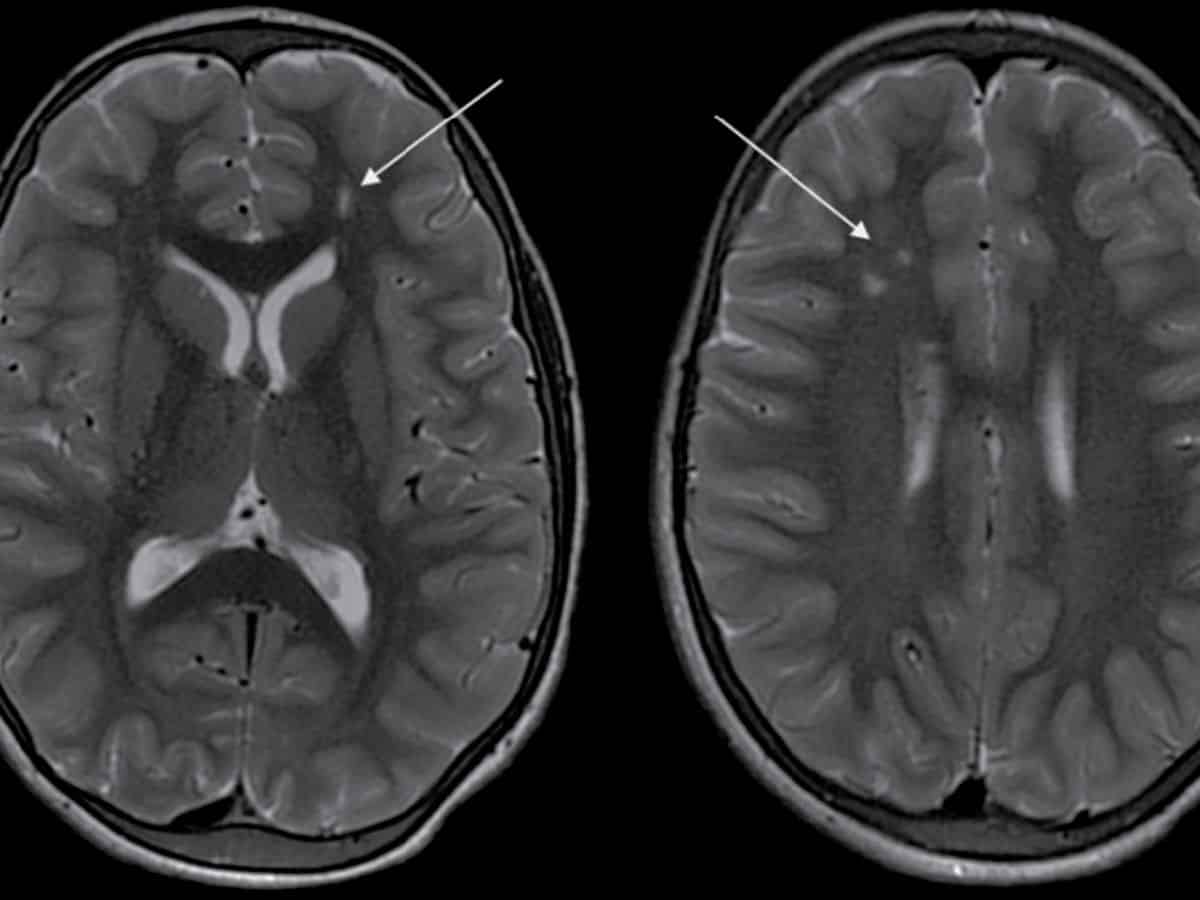

This rare and unique disease mostly affects children around the age of 10 years and adults around the age of 40 years while progressing without warning, necessitating prompt and precise medical intervention. Moyamoya disease causes narrowing of key brain arteries, prompting the brain to form smaller compensatory blood vessels to meet its oxygen needs. These new vessels, however, are often insufficient, appearing as a “puff of smoke” in imaging scans. When the brain’s demand for blood outpaces the supply, patients experience strokes or other neurological events, as in Arjun’s case. Left untreated, Moyamoya can lead to recurring strokes, disability, and even death, making early diagnosis critical to altering the disease's course.